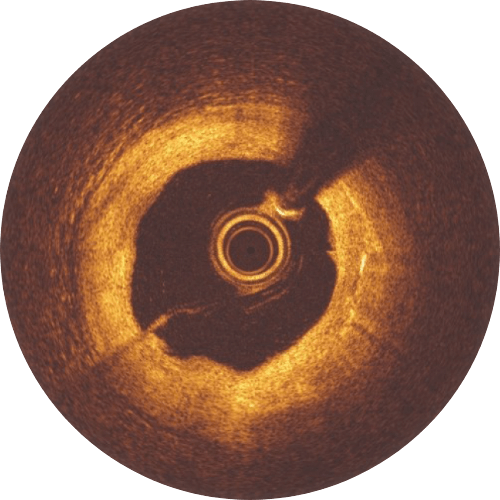

Immediately after Implantation, struts are well apposed to the vessels wall.